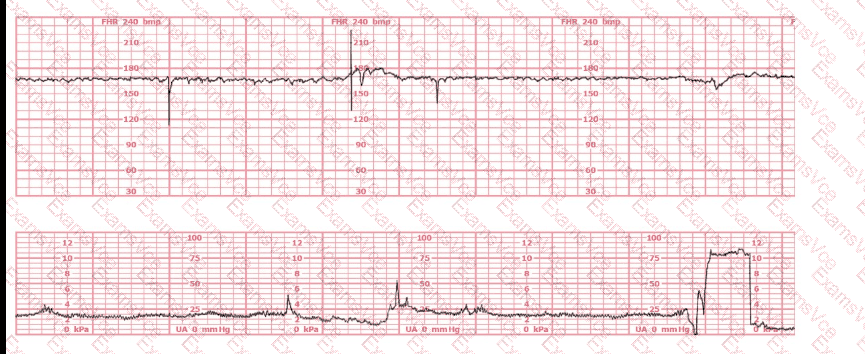

Based on the tracing shown, the first action should be to